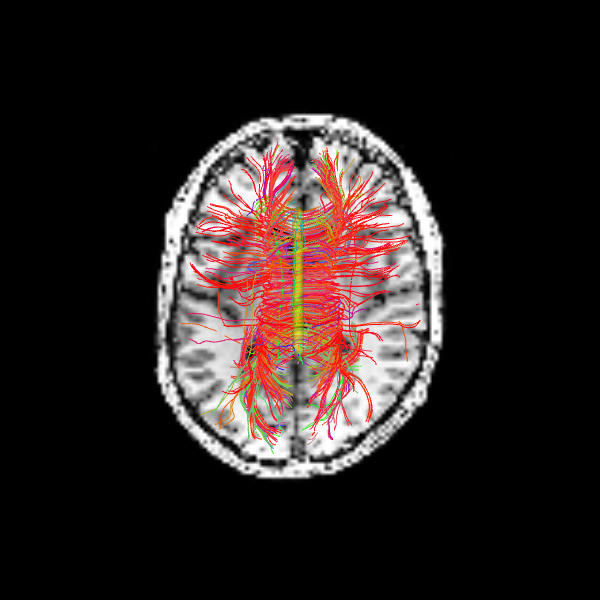

Since we seeded streamlines exclusively from the corpus callosum, all resulting fibers represent interhemispheric connections originating from this region. Let’s visualize them using probabilistic direction getter from SH (peaks_from_model):

scene = window.Scene()

scene.add(actor.line(streamlines_prob, colors=colormap.line_colors(streamlines_prob)))

window.record(scene=scene, out_path="tractogram_probabilistic.png", size=(600, 600))

Image('tractogram_probabilistic.png')

../_images/a3c03b2d897af064f99a933ce57b272dce1f7fce349510a591a2fdb757ebe29d.png